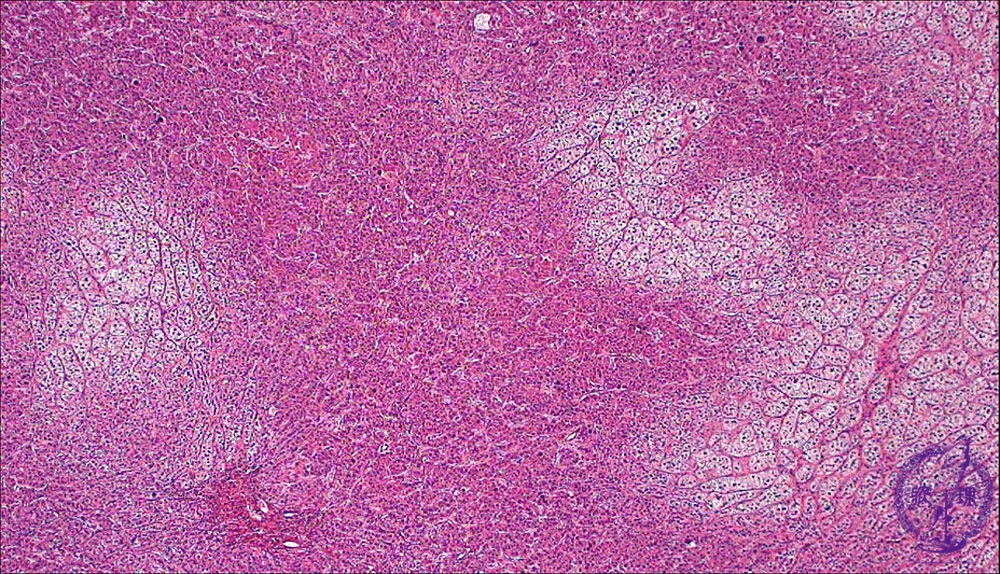

• š(13)Adrenocortical adenoma (Cushing syndrome)

Microscopic findings (HE stain, low power view). The tumor is composed of both clear and eosinophilic cell components.